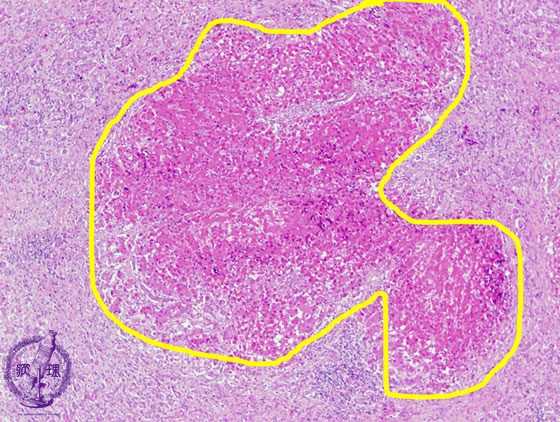

- ★(3)Fulminant hepatitis

Microscopic finding (HE stain, low power view): Irregular necrotic foci show eosinophilic change.